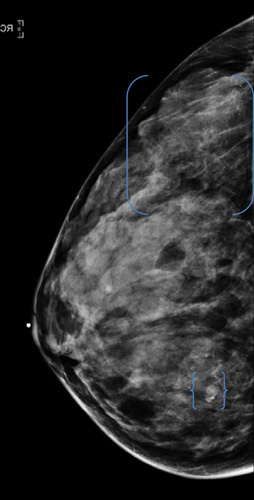

[Caption above and below:Mammography images (from 2010, left; and 2012, right) of a woman in her forties with no family history of breast cancer who missed a year of screening and in the interval developed suspicious right upper out calcifications [ ] and a suspicious mass { }, both of which underwent biopsy, yielding invasive carcinoma.]

Photo Source: Radiologic Society of North America RSNA